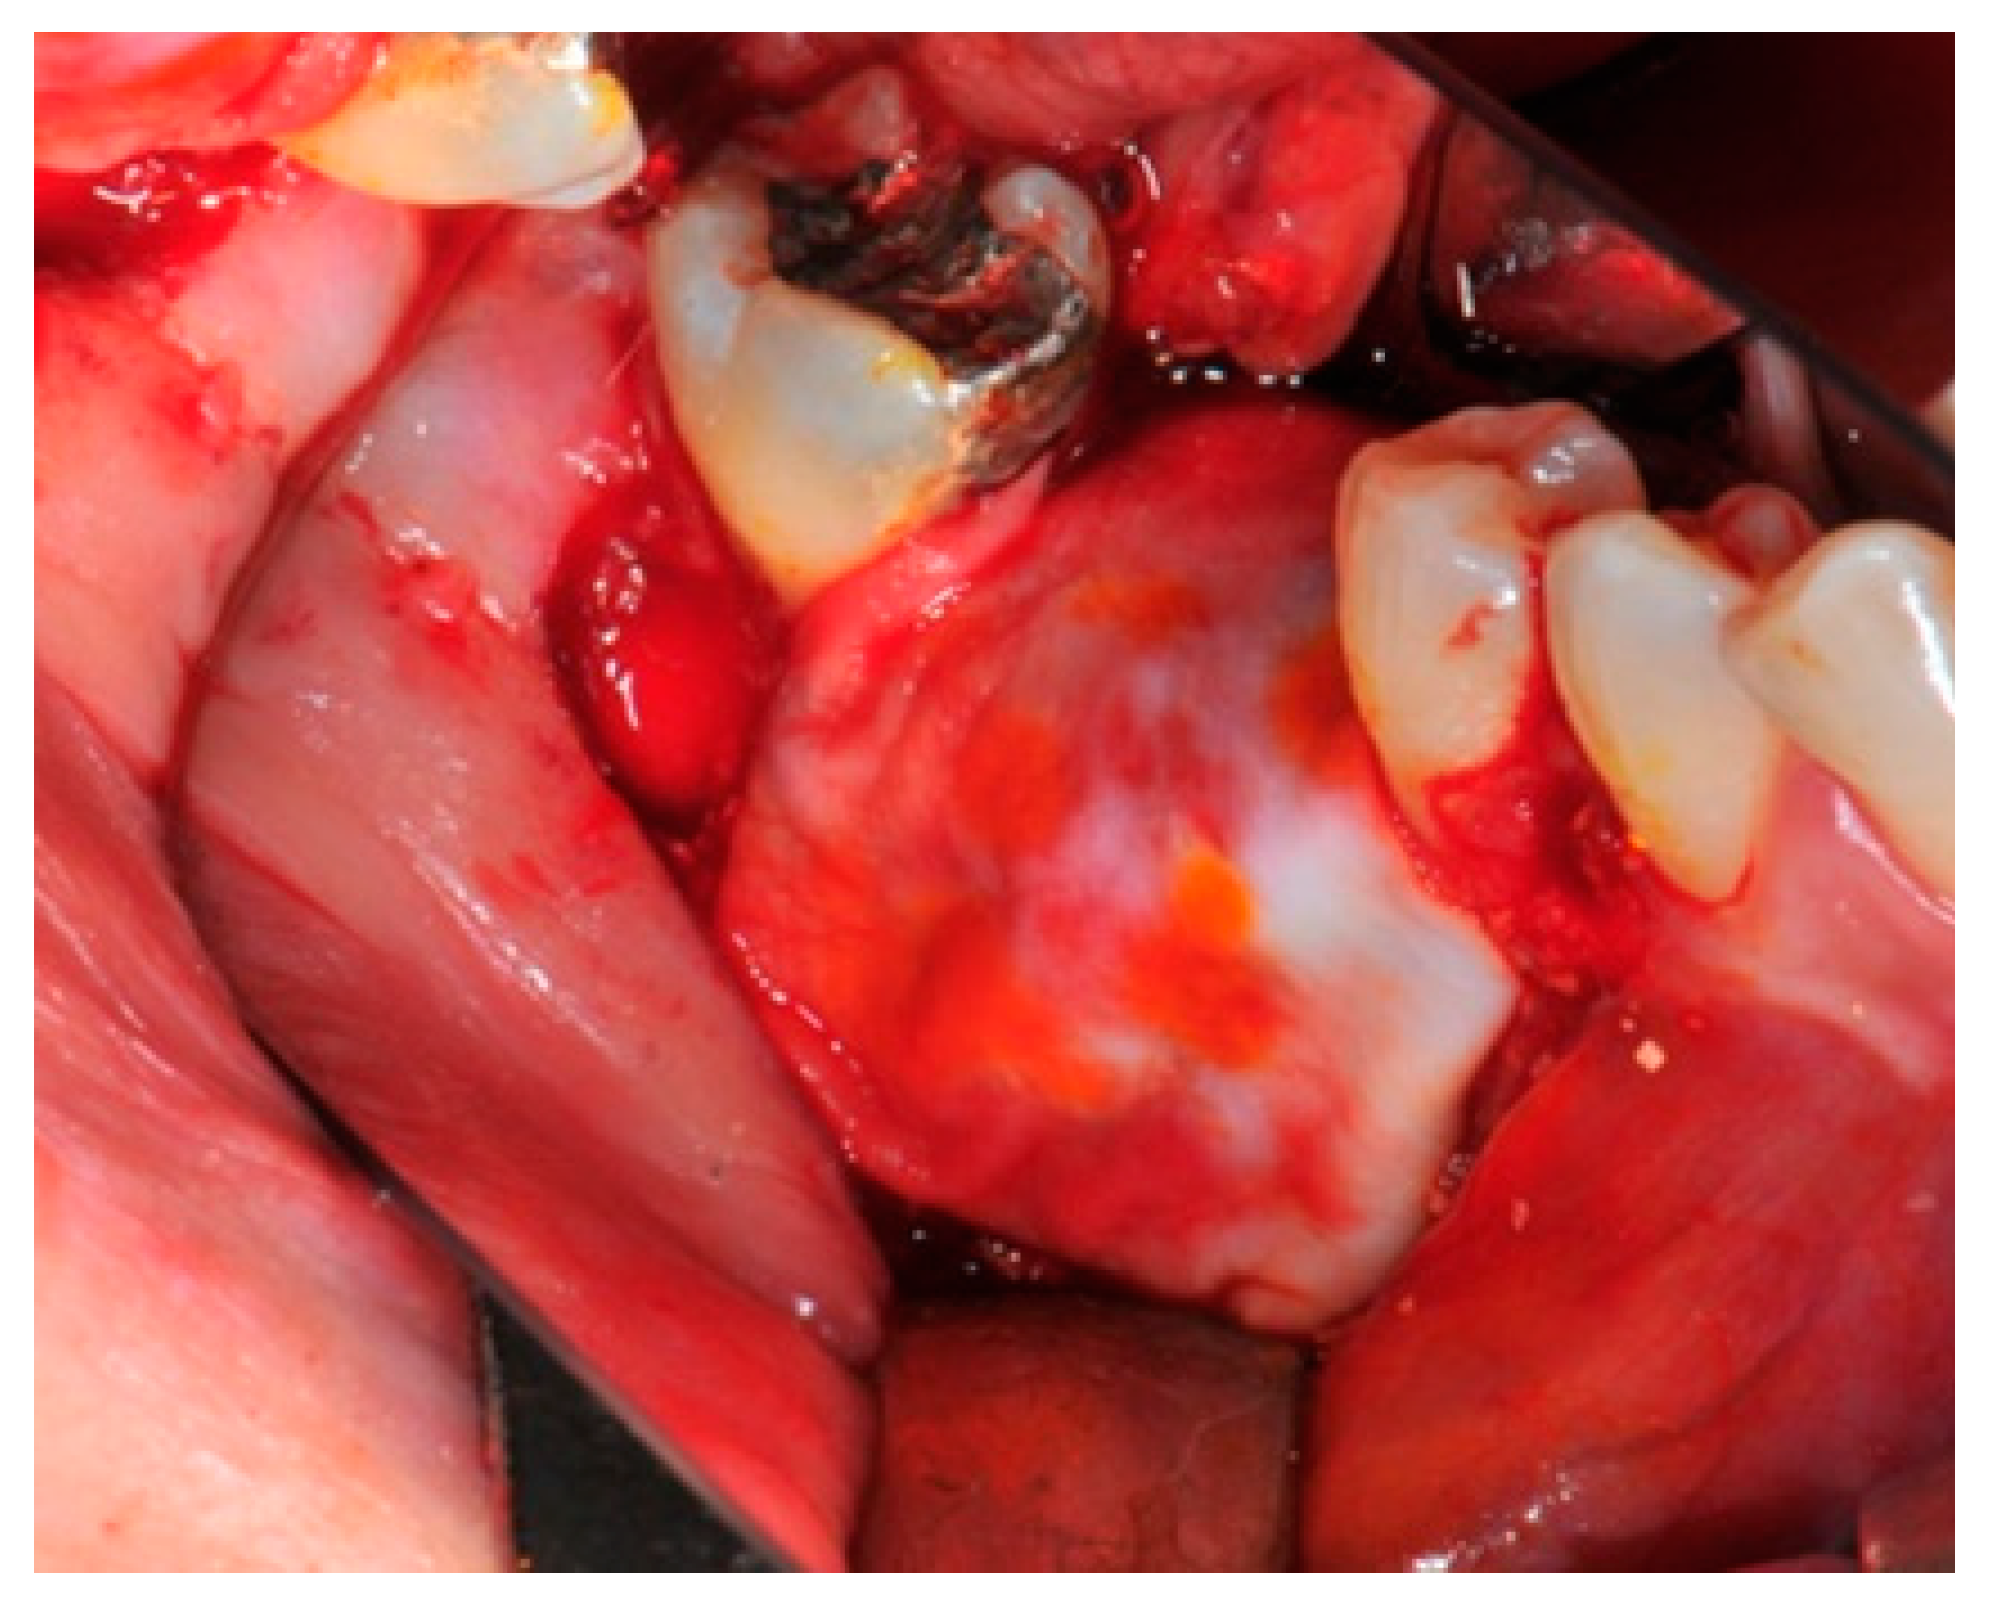

- Particulate bone: At this stage, a 50:50 autologous/heterologous bone mix is grafted both in the atrophic site and within the titanium mesh (Figure 7).